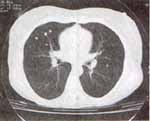

El sedimento urinario se encontró normal, la depuración de creatinina en 50 ml/min, Proteinuria de 143 mg en orina de 24 horas (volumen de 1630 ml), curva flujo volumen normal (Figura 4), Rayos X de manos con calcinosis escasa y el TAC de tórax del 2000 muestra múltiples opacidades nodulares de 1 a 4 mm de diámetro de densidad cálcica dispersas en todo el parénquima pulmonar, sin evidencia de adenopatías ni de hipertensión pulmonar (Figuras 5-7).

Figuras 5-7. TAC de tórax que muestra múltiples opacidades nodulares de 1 a 4 mm de diámetro de densidad cálcica dispersas en todo el parénquima pulmonar, sin otras alteraciones.